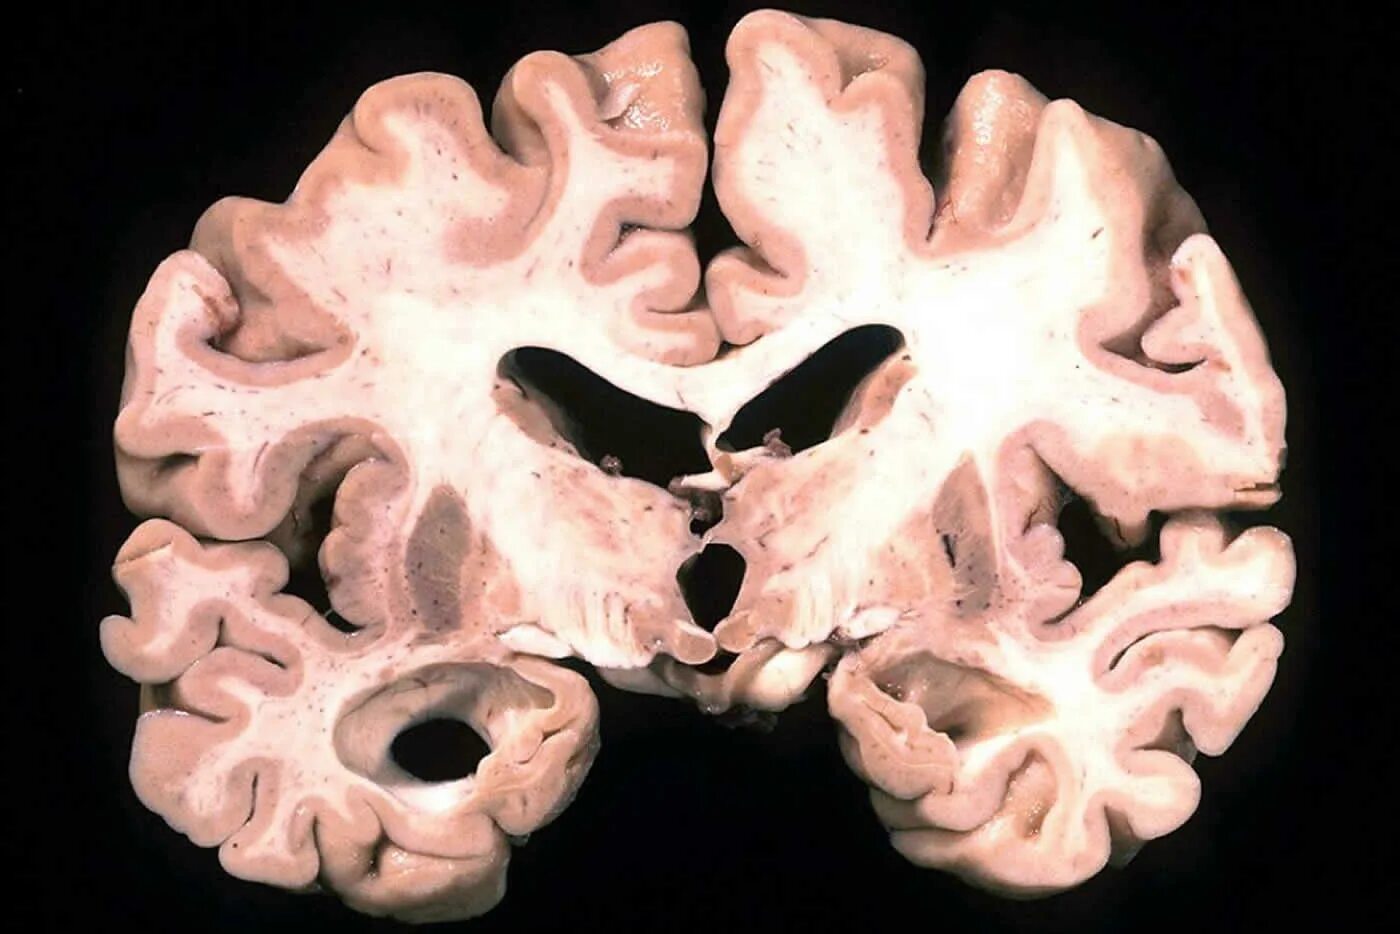

Мозг при деменции